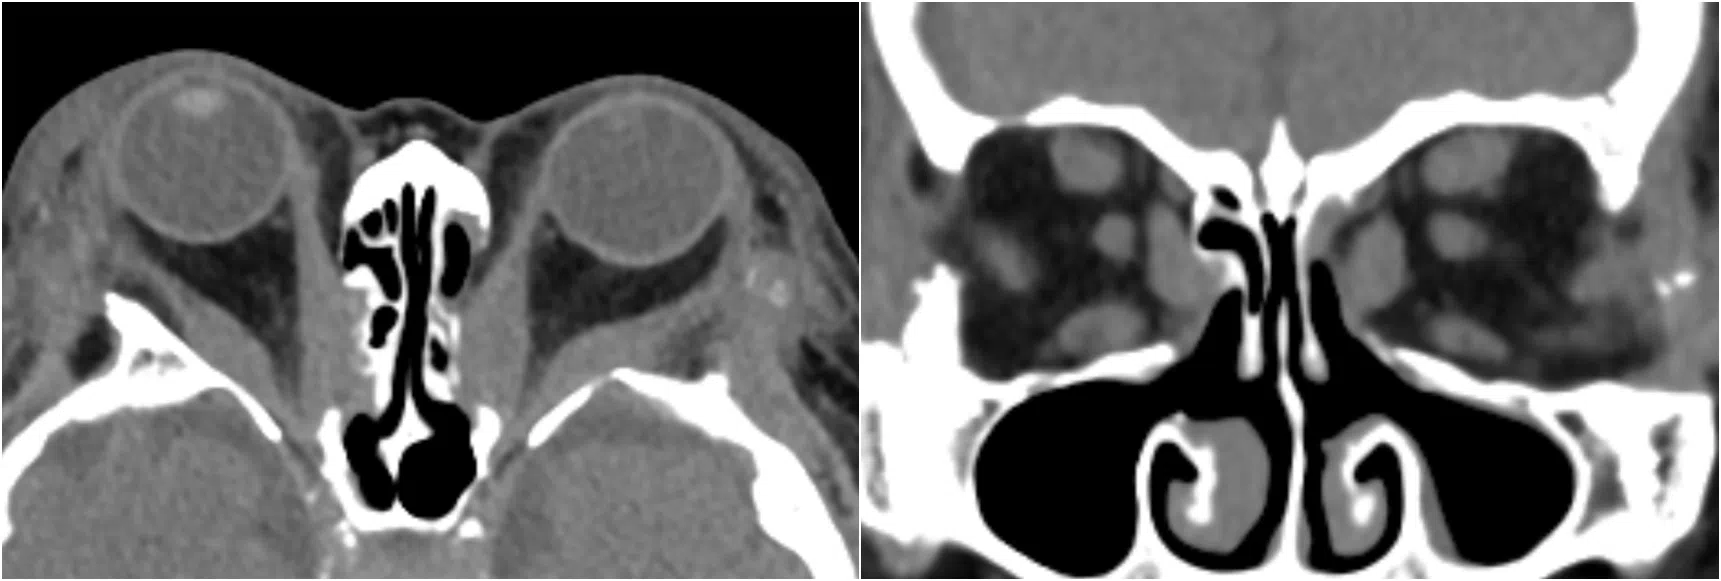

Scan showing a thyroid eye disease patient’s eyeballs bulging out of the eye sockets (left). Working through the nose, surgeons use endoscopes and small instruments to carry out decompression surgery, removing the middle and bottom walls of the bone surrounding the eye (right).

PHOTOS: NUHS